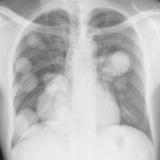

Mets

Album: Mets

Date: 02/18/2006

Size: 52 items

Views: 40032